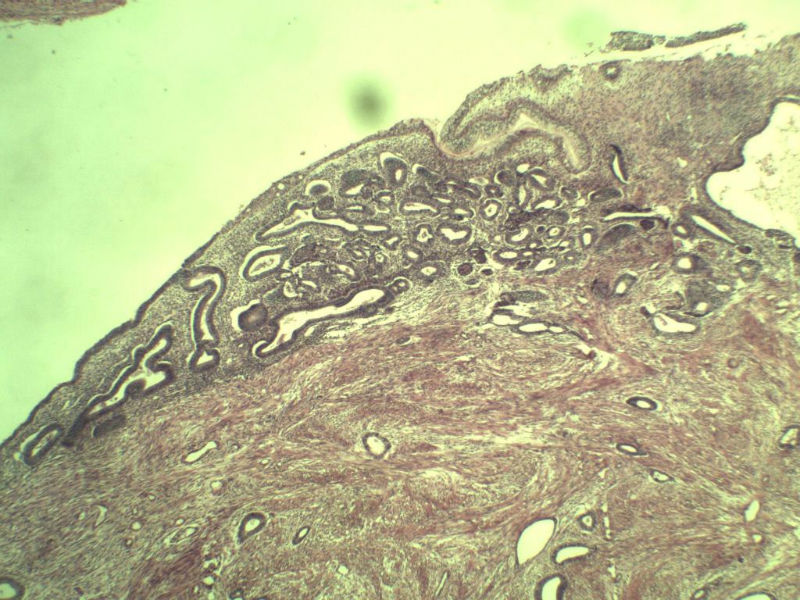

这是子宫内膜  厚0.4cm  看上去没问题

名称:图1

描述:a135.Jpg.jpg

名称:图2

描述:a136.Jpg.jpg

名称:图3

描述:a137.Jpg.jpg

名称:图4

描述:a138.Jpg.jpg

名称:图5

描述:a139.Jpg.jpg

名称:图6

描述:a140.Jpg.jpg

名称:图7

描述:a141.Jpg.jpg

名称:图8

描述:a142.Jpg.jpg

名称:图9

描述:a143.Jpg.jpg